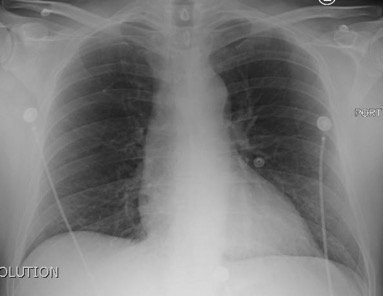

Chest x-ray and CT angiogram was performed to evaluate his thoracic and abdominal vasculature. Chest x-ray did not show any significant widening of the mediastinum. The CT angiogram demonstrated an intimal tear along the aortic arch separating a true and false aortic lumen, consistent with an acute aortic dissection. The true lumen (highlighted in blue in images 1-5) can be identified by continuity with an undissected part of the aorta1. While the false lumen (highlighted in red in images 1-5) can be identified by its crescent shape and larger cross-sectional area.1